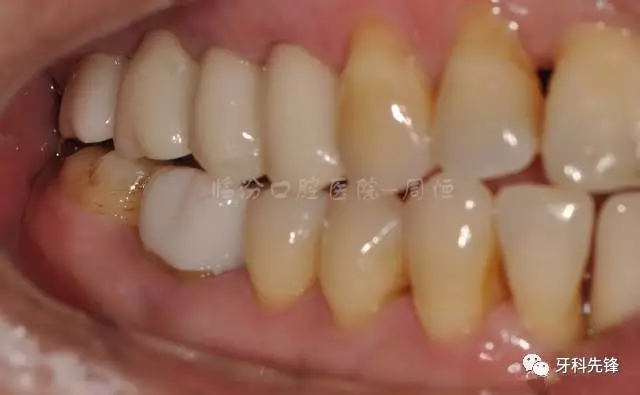

圖2  術(shù)前側(cè)位咬頜照

640.webp (3).jpg